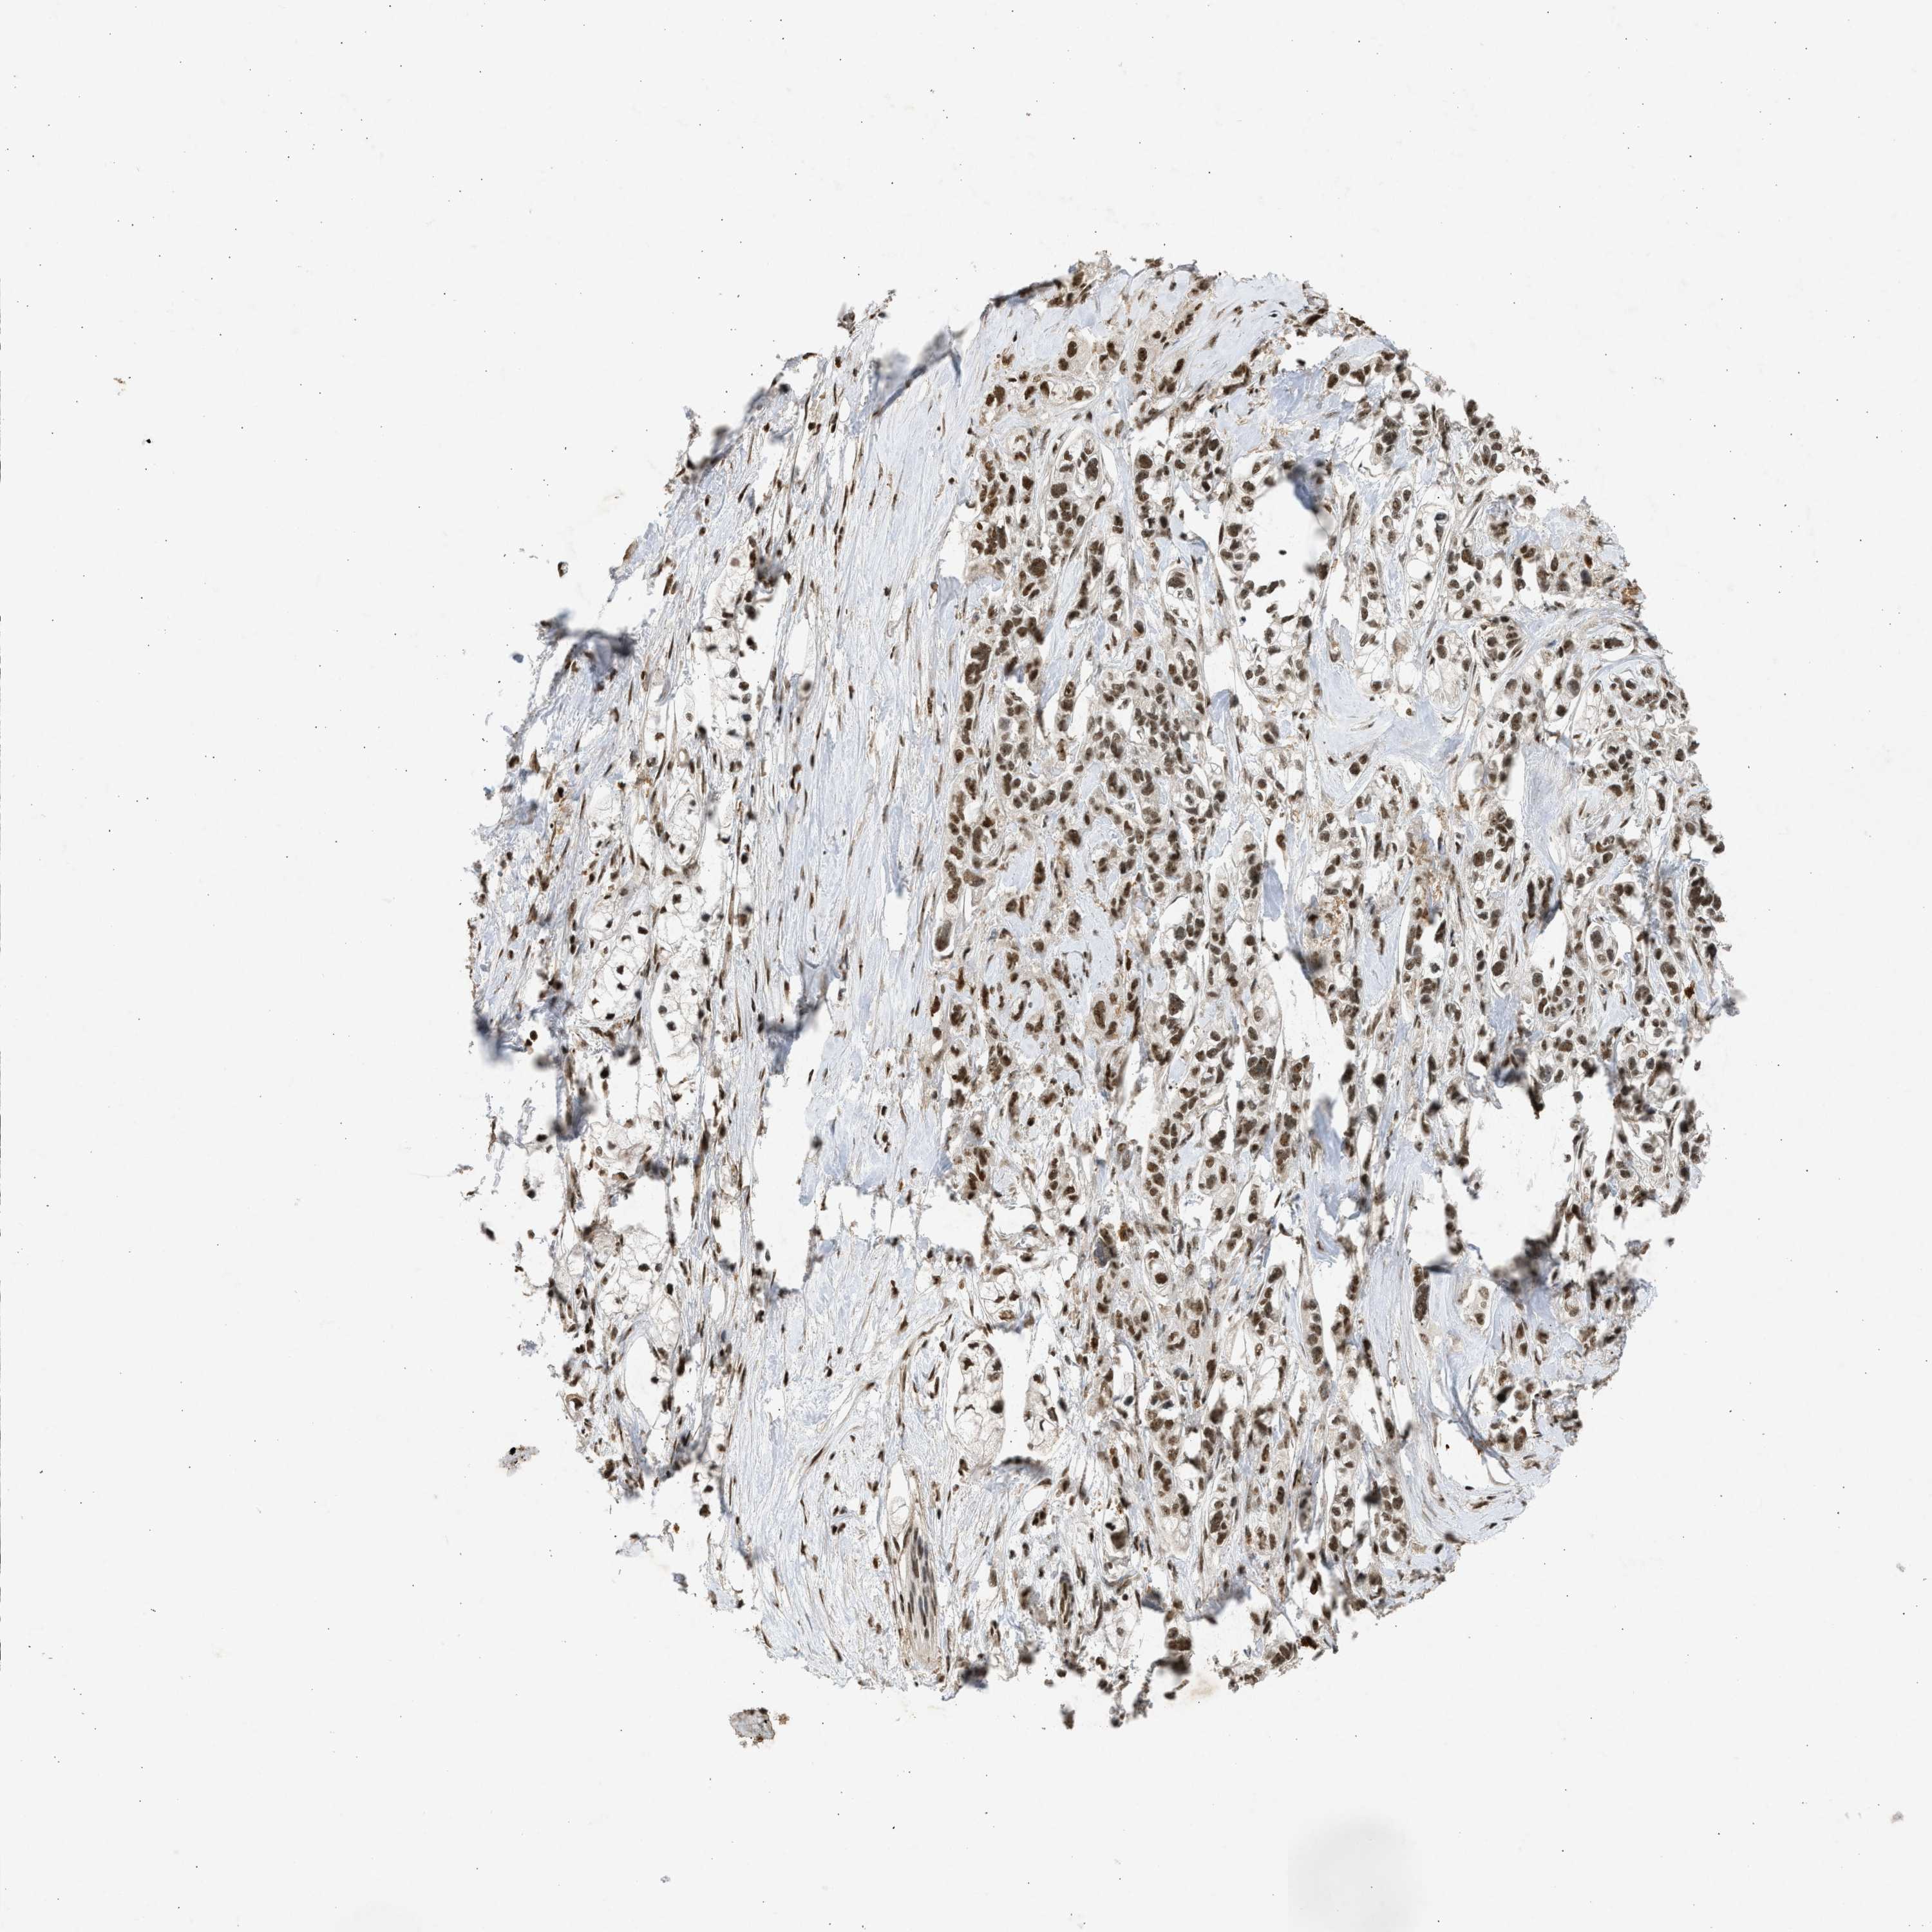

PANCREATIC CANCER - Protein expressioni

A mouse-over function shows sample information and annotation data. Click on an image to view it in a full screen mode. Samples can be filtered based on level of antibody staining by selecting one or several of the following categories: high, medium, low and not detected. The assay and annotation is described here.

Note that samples used for immunohistochemistry by the Human Protein Atlas do not correspond to samples in the TCGA dataset.

Antibody stainingi

Antibody staining in the annotated cell types in the current human tissue is reported as not detected, low, medium, or high, based on conventional immunohistochemistry profiling in selected tissues. This score is based on the combination of the staining intensity and fraction of stained cells.

Each image is clickable and will lead to virtual microscopy that enables deeper exploration of all samples and also displays staining intensity scores, fraction scores and subcellular localization as well as patient and tissue information for each sample.

Antibody CAB018396

Staining

High

Medium

Low

Not detected

Intensity

Strong

Moderate

Weak

Negative

Quantity

>75%

75%-25%

<25%

None

Location

Nuclear

Cytoplasmic/membranous

Cytoplasmic/membranous,nuclear

Adenocarcinoma, NOS